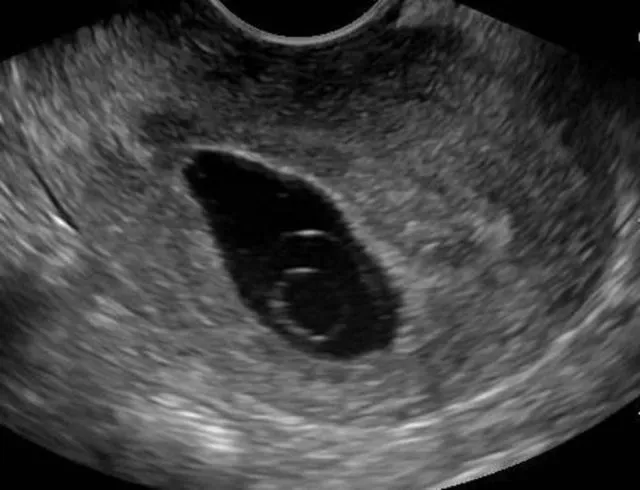

Blighted ovum, atau kehamilan anembrionik, adalah jenis keguguran yang terjadi sangat dini dalam kehamilan. Kondisi ini terjadi saat sel telur yang sudah dibuahi berhasil menempel di dinding rahim, tetapi tidak berkembang menjadi embrio. Akibatnya, kantung kehamilan tetap kosong dan akhirnya menyebabkan keguguran pada trimester pertama.

Blighted ovum termasuk salah satu penyebab utama keguguran pada trimester pertama. Menurut Cleveland Clinic, kondisi ini bisa terjadi sebelum seseorang menyadari dirinya sedang hamil. Meskipun tidak ada embrio yang terbentuk, tubuh tetap menghasilkan hormon kehamilan karena kantung kehamilan dan plasenta tetap tumbuh. Ini menyebabkan gejala kehamilan awal seperti mual, nyeri payudara, dan bahkan hasil tes kehamilan positif.